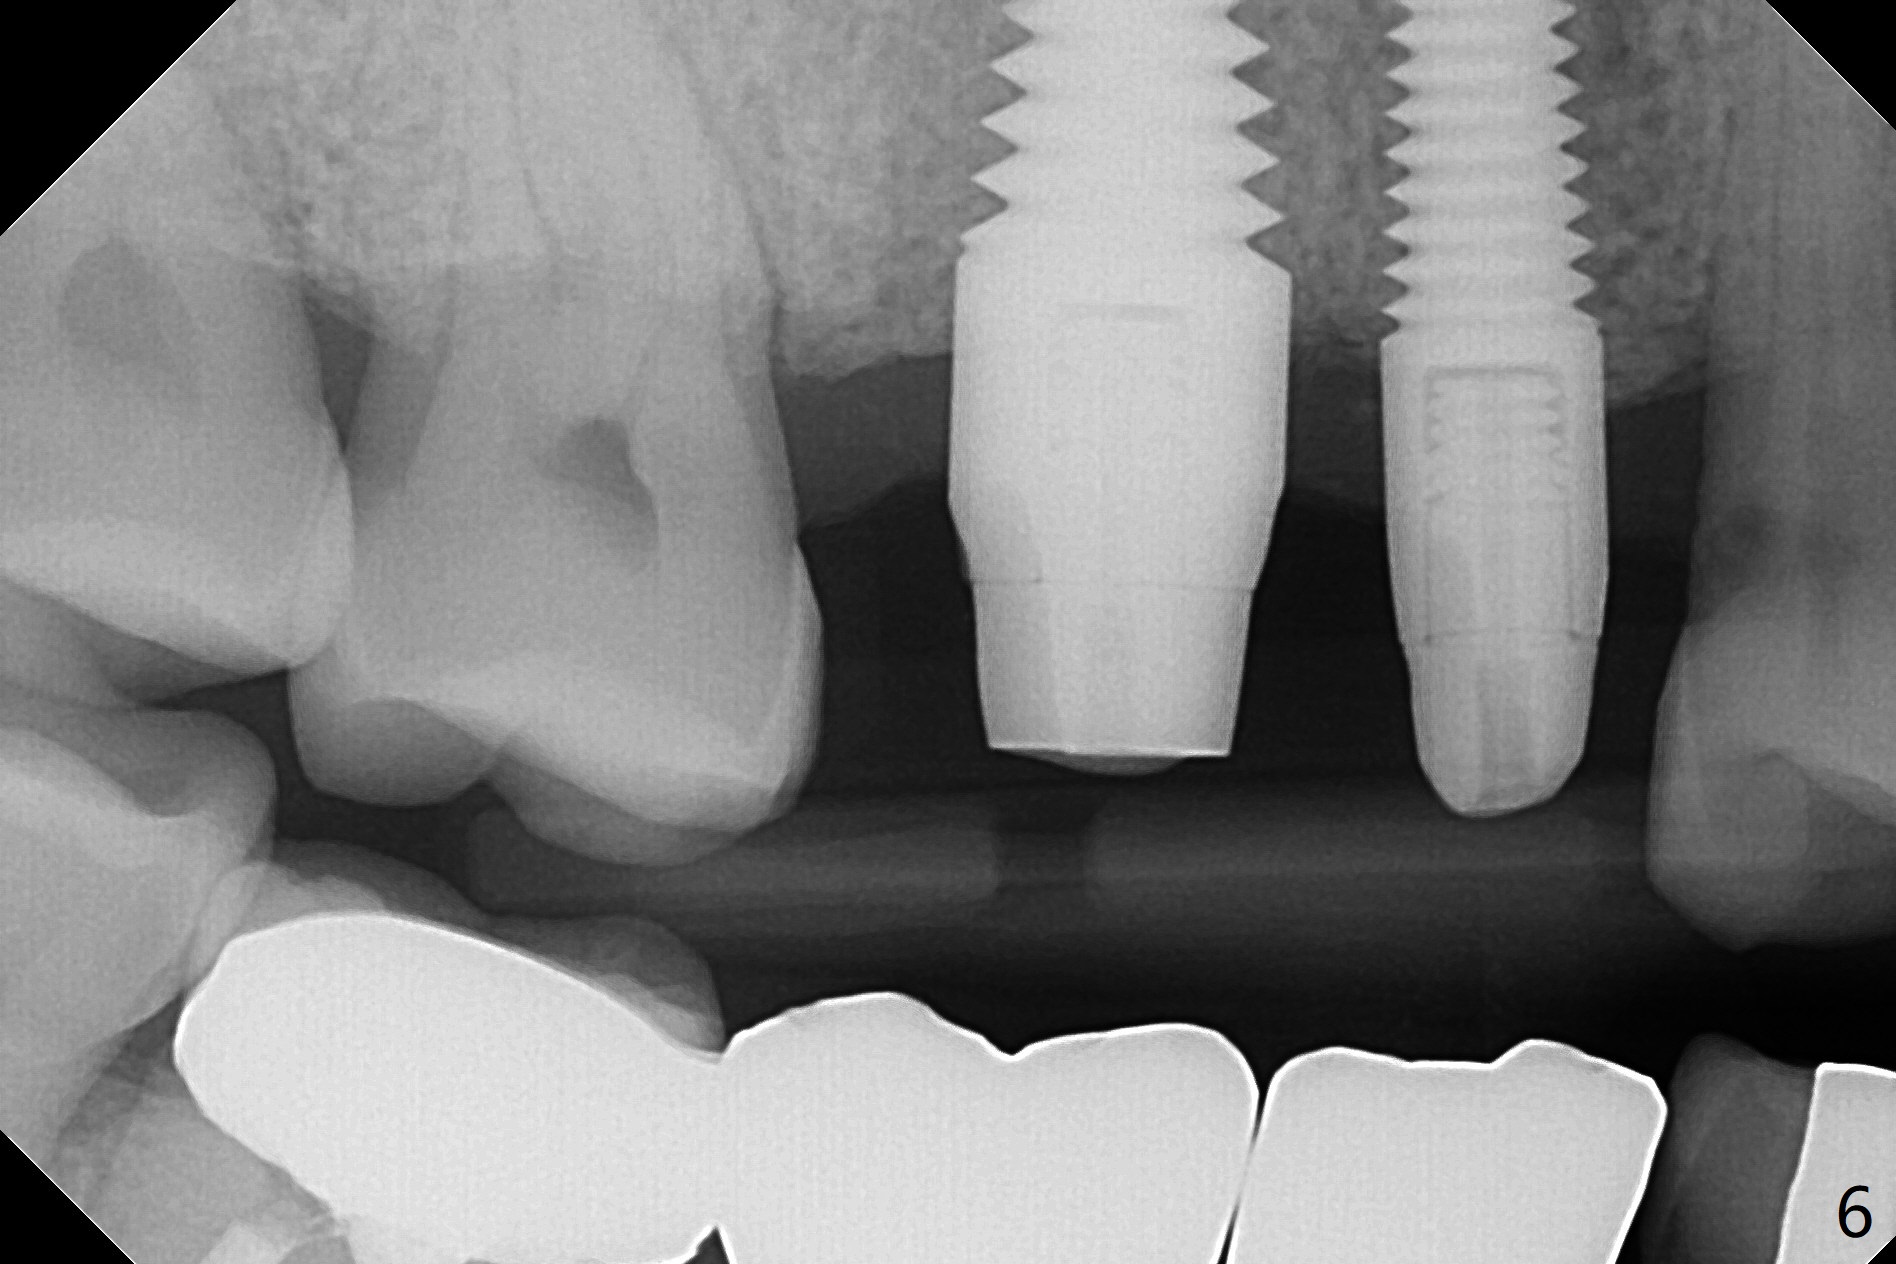

With proper manipulation, a 6x14 mm implant is placed with primary stability (Fig.3). The buccal and palatal socket opening is closed with Vera Graft (allograft, Fig.4 *), which is in turn covered by an immediate splinted provisional. No gap exists 7 months postop (Fig.5,6). Return to Upper Molar Immediate Implant, Prevent Molar Periimplantitis (Protocols, Table), IBS Xin Wei, DDS, PhD, MS 1st edition 09/26/2017, last revision 04/24/2018